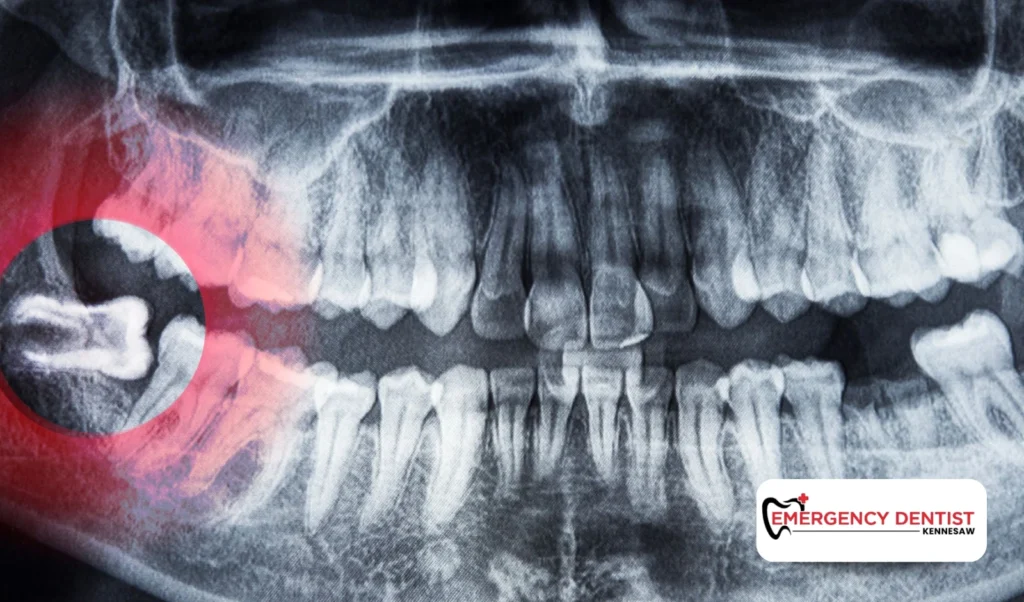

An impacted wisdom tooth does not fully emerge through the gums. It may grow at an angle or press against other teeth. These situations often require oral surgery techniques.

Because more time and planning are involved, impacted cases tend to increase the average cost of a wisdom tooth removal. When people ask, how much is a wisdom tooth extraction, the answer often depends on whether the tooth is impacted or fully erupted.

During your visit, the dentist will:

• Take diagnostic X-rays

• Determine the type of extraction needed

• Evaluate whether oral surgery is required